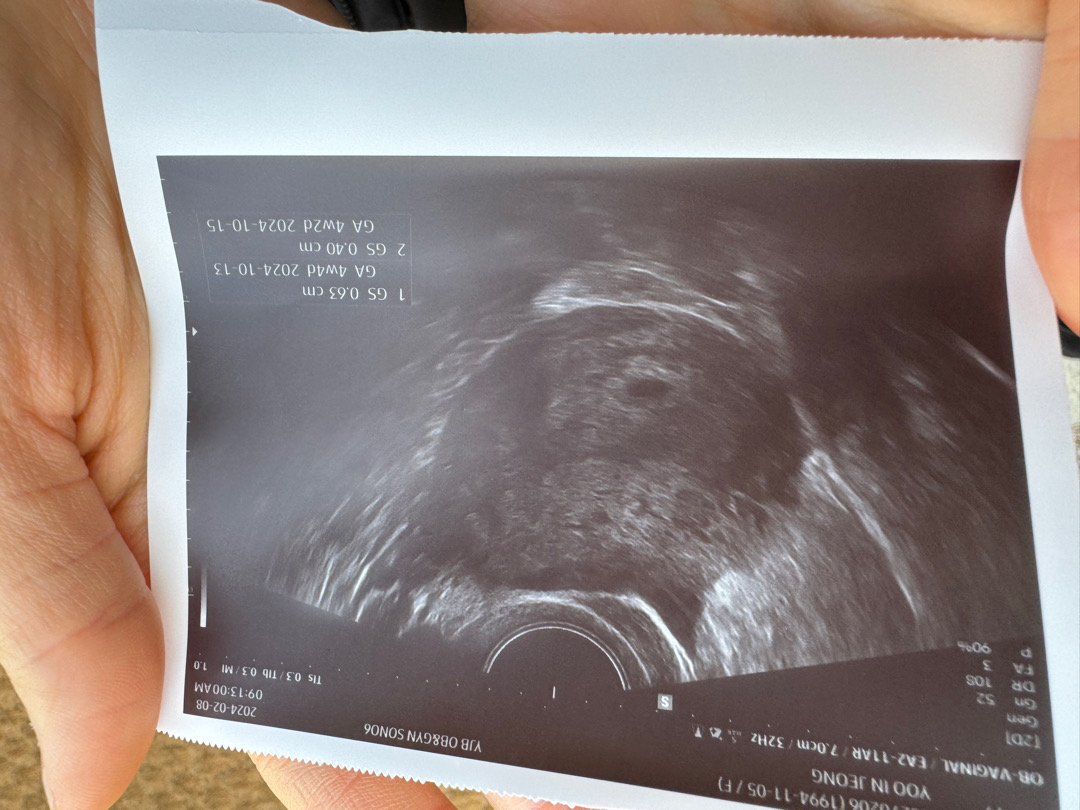

아기집 보고왔어요🥹

막생1월4일 오늘 딱 5주차0일 좀 빠르게가서 아기집 못보면 어떡하지 걱정하면서 다녀왔는데 다행히 아기집 보고왔네요! 병원에서는 4주차6일이라고하네요 ㅎㅎ아쉽게 난황은 못봐서 ㅠ다음주 주말에 오라고 했는데 그때는 난황+심장소리까지 들을 수 있을까요!?🥹

저는 0.5요!! 몇이세요!?